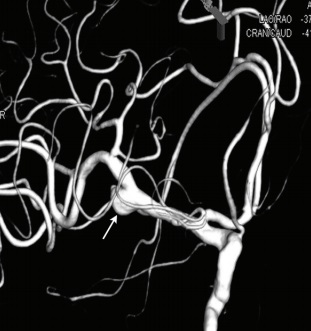

A씨에게서 발견된 동맥류(화살표)의 모습./사진=대한신경과학회지 단신 보고 '실데나필 복용 후 발생한 동맥류 파열에 의한 지주막하출혈'

65세 남성 A씨는 발기부전약(실데나필) 50mg을 먹고난 뒤 20분 정도 지나자, 갑자기 심한 두통이 생겼고 말이 어눌해졌다. 다음날에도 두통이 지속되고 의식마저 점차 저하되자 A씨는 응급실을 찾았다. 검사 결과, 뇌동맥류 파열이 원인이었고 바로 코일색전술을 받았다. 이후 증상은 점차 나아졌지만 지남력과 인지기능이 떨어졌고, 전반적인 근력저하, 삼킴장애 등이 남은 상태로 3개월 후 퇴원했다.

발기부전약을 복용한 후 뇌동맥류 파열에 의한 지주막하출혈이 발생한 국내 첫 사례가 보고됐다. 지주막하출혈은 뇌의 지주막 아래 공간에 뇌출혈이 일어나는 질환을 말한다. 동맥류는 혈관벽의 약한 부위가 혈압에 의해 밖으로 팽창돼서 형성된 주머니다. A씨와 같은 동맥류 파열은 보통 자연적으로 일어나지만, 갑자기 혈압이 상승하는 경우에도 발생할 수 있다. 사례 보고한 단국대병원 신경과 송영목 교수는 논문을 통해 "발기부전약을 먹고 성행위 중에 동맥류 파열이 보고된 경우는 있으나, A씨처럼 성행위 없이 약물 복용만으로 발생한 케이스는 없었다"며 "발기부전약(실데나필)과 동맥류 파열에 의한 지주막하출혈과의 인관 관계를 좀 더 명확히 보여주는 사례"라고 말했다. 그는 또는 "A씨의 경우 실데나필에 의한 뇌혈관 확장과 이로 인한 뇌혈류 증가가 동맥류 파열의 원인이었을 것으로 추정한다"고 말했다.